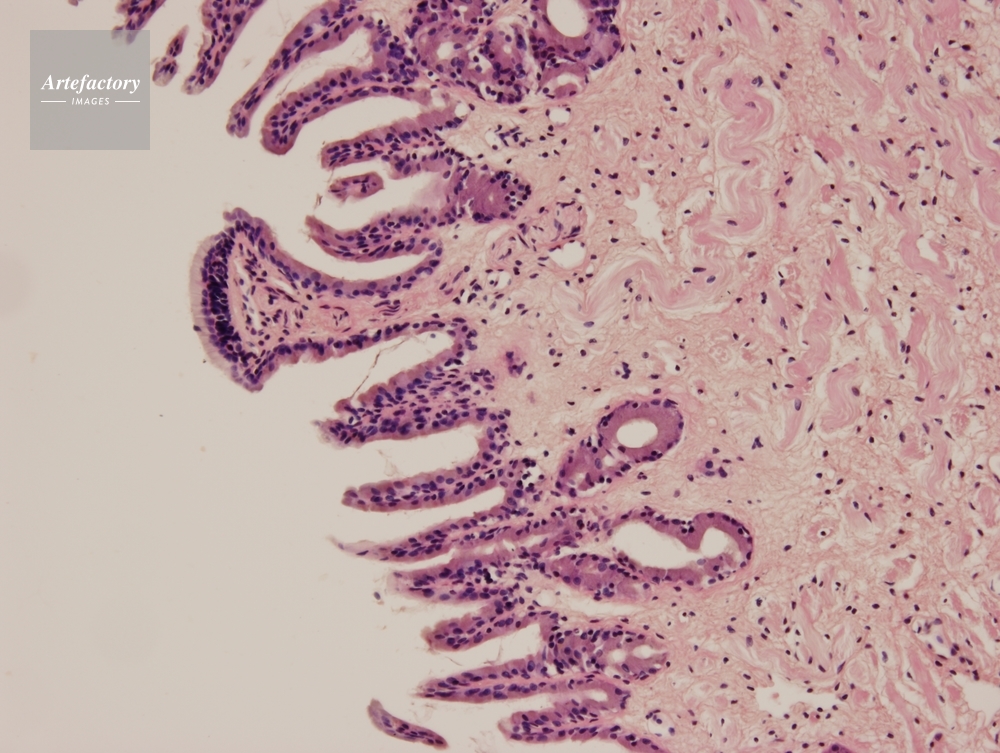

| 作品タイトル | ウシガエル 舌 | モデルリリース | なし | |

| 作家 | OLYMPUS CORPORATION Technolab | プロパティリリース | なし | |